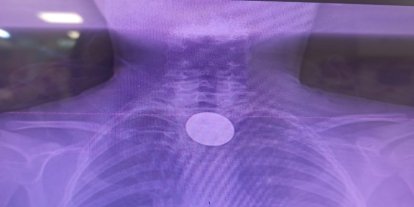

Bursa Şehir Hastanesi’nde görevli girişimsel radyoloji uzmanları Doç. Dr. Furkan Ertürk Urfalı ve Uzm. Dr. Fatih Hakan Tufanoğlu tarafından verilen eğitime Cezayir’den 15 hekim katıldı. Tiroid ve paratiroid hastalıklarında Mikrodalga Ablasyon (MWA) tedavileri ele alındığı eğitimde güncel literatür bilgileri canlı vaka uygulamalarıyla desteklenerek, katılımcılara aktarıldı.

Bursa Şehir Hastanesi Girişimsel Radyoloji Birimi’nin girişimsel radyolojinin pek çok alanında önemli bir merkez haline geldiğini belirten Doç. Dr. Furkan Ertürk Urfalı, uygun hastalarda tiroid ve paratiroid hastalıklarının genel anestezi ve cerrahi gerektirmeden, lokal anestezi altında bir iğne ile uygulanan mikrodalga ablasyon yöntemleriyle (yakma) tedavi edilebileceğini belirtti.